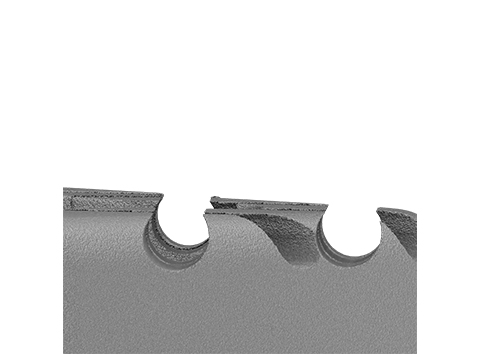

Spine/Surface Technology

Reef Topography™

Undercut macrostructures designed to promote bony interlocking

• Endplate features place graft material in direct contact with the endplates.

• Aperture features secure graft within the aperture during interbody placement.

• Undercut macrostructures results in ~3x increase in mechanical stability